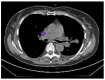

Lymphadenectomy represents a fundamental step in the staging and treatment of non-small cell lung cancer (NSCLC). To date, the extension of lymphadenectomy in early-stage NSCLC is a debated topic due to its possible complications. The detection of sentinel lymph nodes (SLNs) is a strategy that can improve the selection of patients in which a more extended lymphadenectomy is necessary. This pilot study aimed to refine lymph nodal staging in early-stage NSCLC patients who underwent robotic lung resection through the application of innovative intraoperative sentinel lymph node (SLN) identification and the pathological evaluation using one-step nucleic acid amplification (OSNA). Clinical N0 NSCLC patients planning to undergo robotic lung resection were selected. The day before surgery, all patients underwent radionuclide computed tomography (CT)-guided marking of the primary lung lesion and subsequently Single Photon Emission Computed Tomography (SPECT) to identify tracer migration and, consequently, the area with higher radioactivity. On the day of surgery, the lymph nodal radioactivity was detected intraoperatively using a gamma camera. SLN was defined as the lymph node with the highest numerical value of radioactivity. The OSNA amplification, detecting the mRNA of CK19, was used for the detection of nodal metastases in the lymph nodes, including SLN. From March to July 2021, a total of 8 patients (3 female; 5 male), with a mean age of 66 years (range 48-77), were enrolled in the study. No complications relating to the CT-guided marking or preoperative SPECT were found. An average of 5.3 lymph nodal stations were examined (range 2-8). N2 positivity was found in 3 out of 8 patients (37.5%). Consequently, pathological examination of lymph nodes with OSNA resulted in three upstages from the clinical IB stage to pathological IIIA stage. Moreover, in 1 patient (18%) with nodal upstaging, a positive node was intraoperatively identified as SLN. Comparing this protocol to the usual practice, no difference was found in terms of the operating time, conversion rate, and complication rate. Our preliminary experience suggests that sentinel lymph node detection, in association with the accurate pathological staging of cN0 patients achieved using OSNA, is safe and effective in the identification of metastasis, which is usually undetected by standard diagnostic methods.